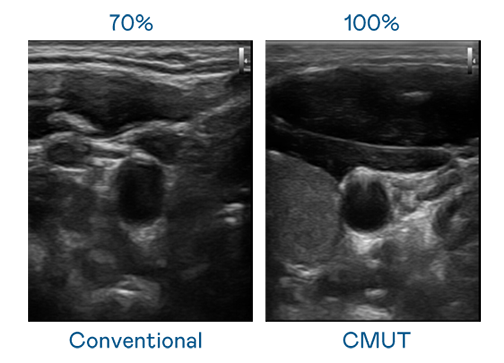

CMUT 技术是一种用电容式微机电元件来产生超音波讯号的技术。与传统 PZT 压电式技术相比,CMUT 频宽增加 30%,更宽频的超音波讯号让影像解析度大幅提升,是实现高影像品质医疗超音波扫描、促进精准医疗发展的关键技术。

大频宽带来超清晰影像

超音波影像的解析度高低,首先取决于探头能发出的讯号频宽。凯发k8官方网站登录 CMUT 可提供高清晰的超音波讯号,提供高频宽、高灵敏度、影像纹理细节更高的超音波影像,协助医护人员缩短影像判读时间及利用精准的医疗影像进行诊断。